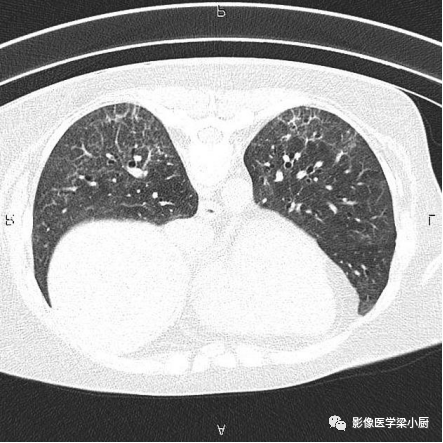

1.分布:90%的IPF患者HRCT表现为胸膜下分布。

分布的不均匀性:HRCT肺外周部位和胸膜下区不均匀分布,正常肺组织和病变区(网格、牵拉性支气管扩张或蜂窝)交替。病变常呈双侧不对称分布。

2.网格:网格影一般分布于两肺基底部、胸膜下,常伴结构扭曲。网格影不等同于小叶间隔增厚。

双肺底弥漫性网格状改变